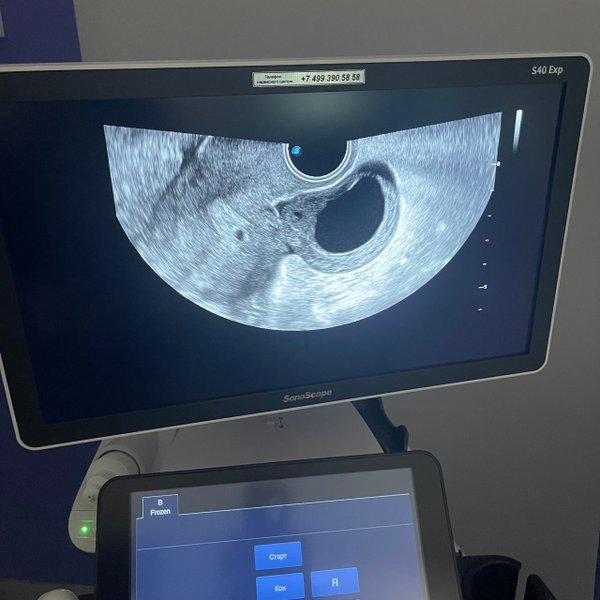

Бородулина Наталья (Врач УЗИ, Косметология) (05.12.2024): #беременность малого срока (продолжение..) ⠀ Что будет сначала видно на #узи осмотре Кто ходил в ранних сроках на узи знает, что эмбрион виден не сразу. Сначала видно плодное яйцо, потом появляется желточный мешочек, и последним появляется эмбрион. ⠀ Плодное яйцо в матке начинает достоверно визуализироваться при размере от 4 мм. ⠀ ️С какой скоростью должно расти плодное яйцо в норме? 0,8—1,2 мм/сут ⠀ ️Когда появляется сердцебиение у эмбриона? При размере его 5—7 мм! ⠀ ️Когда дол… — Читать дальше

жен появиться эмбрион в плодном яйце? При диаметре плодного яйца 16—24 мм Вот такие дела

Бородулина Наталья (Врач УЗИ, Косметология) (04.12.2024): Вы сделали тест на беременность и он показал // две полоски! ‼️ Но не спешите бежать на узи. Вы должны понимать, что плодное яйцо на #узи мы увидим не ранее, чем через 5—7, а часто и 10 дней задержки! ⠀ Почему же тест положительный, а на узи не видно? ⠀Потому, что тест улавливает ХГЧ (гормон #беременных) практически через 3 дня после имплантации (внедрении) плодного яйца в полость матки (в теории это 9—10 день после овуляции и 24 день цикла). Т.е. ещё даже до задержки. Это я рассмотре… — Читать дальше

ла цикл 28 дней. И конечно же, если цикл более длинный, #овуляция позже и тогда день овуляции, а следовательно и имплантации смещается.